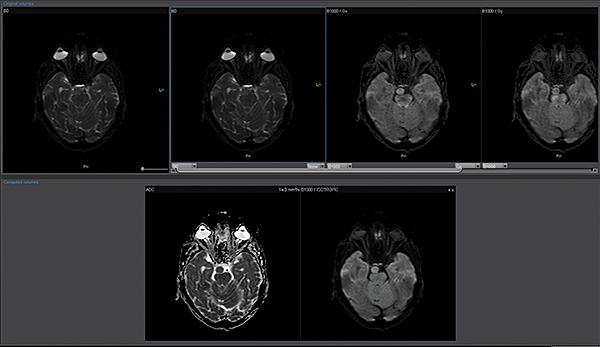

Дифузійно-зважена візуалізація (DWI)

Додаток DWI обробляє ізотропні зображення з кожного окремого коефіцієнта дифузії. Він обчислює параметричні карти, такі як карти ADC та експоненціальні карти ADC.